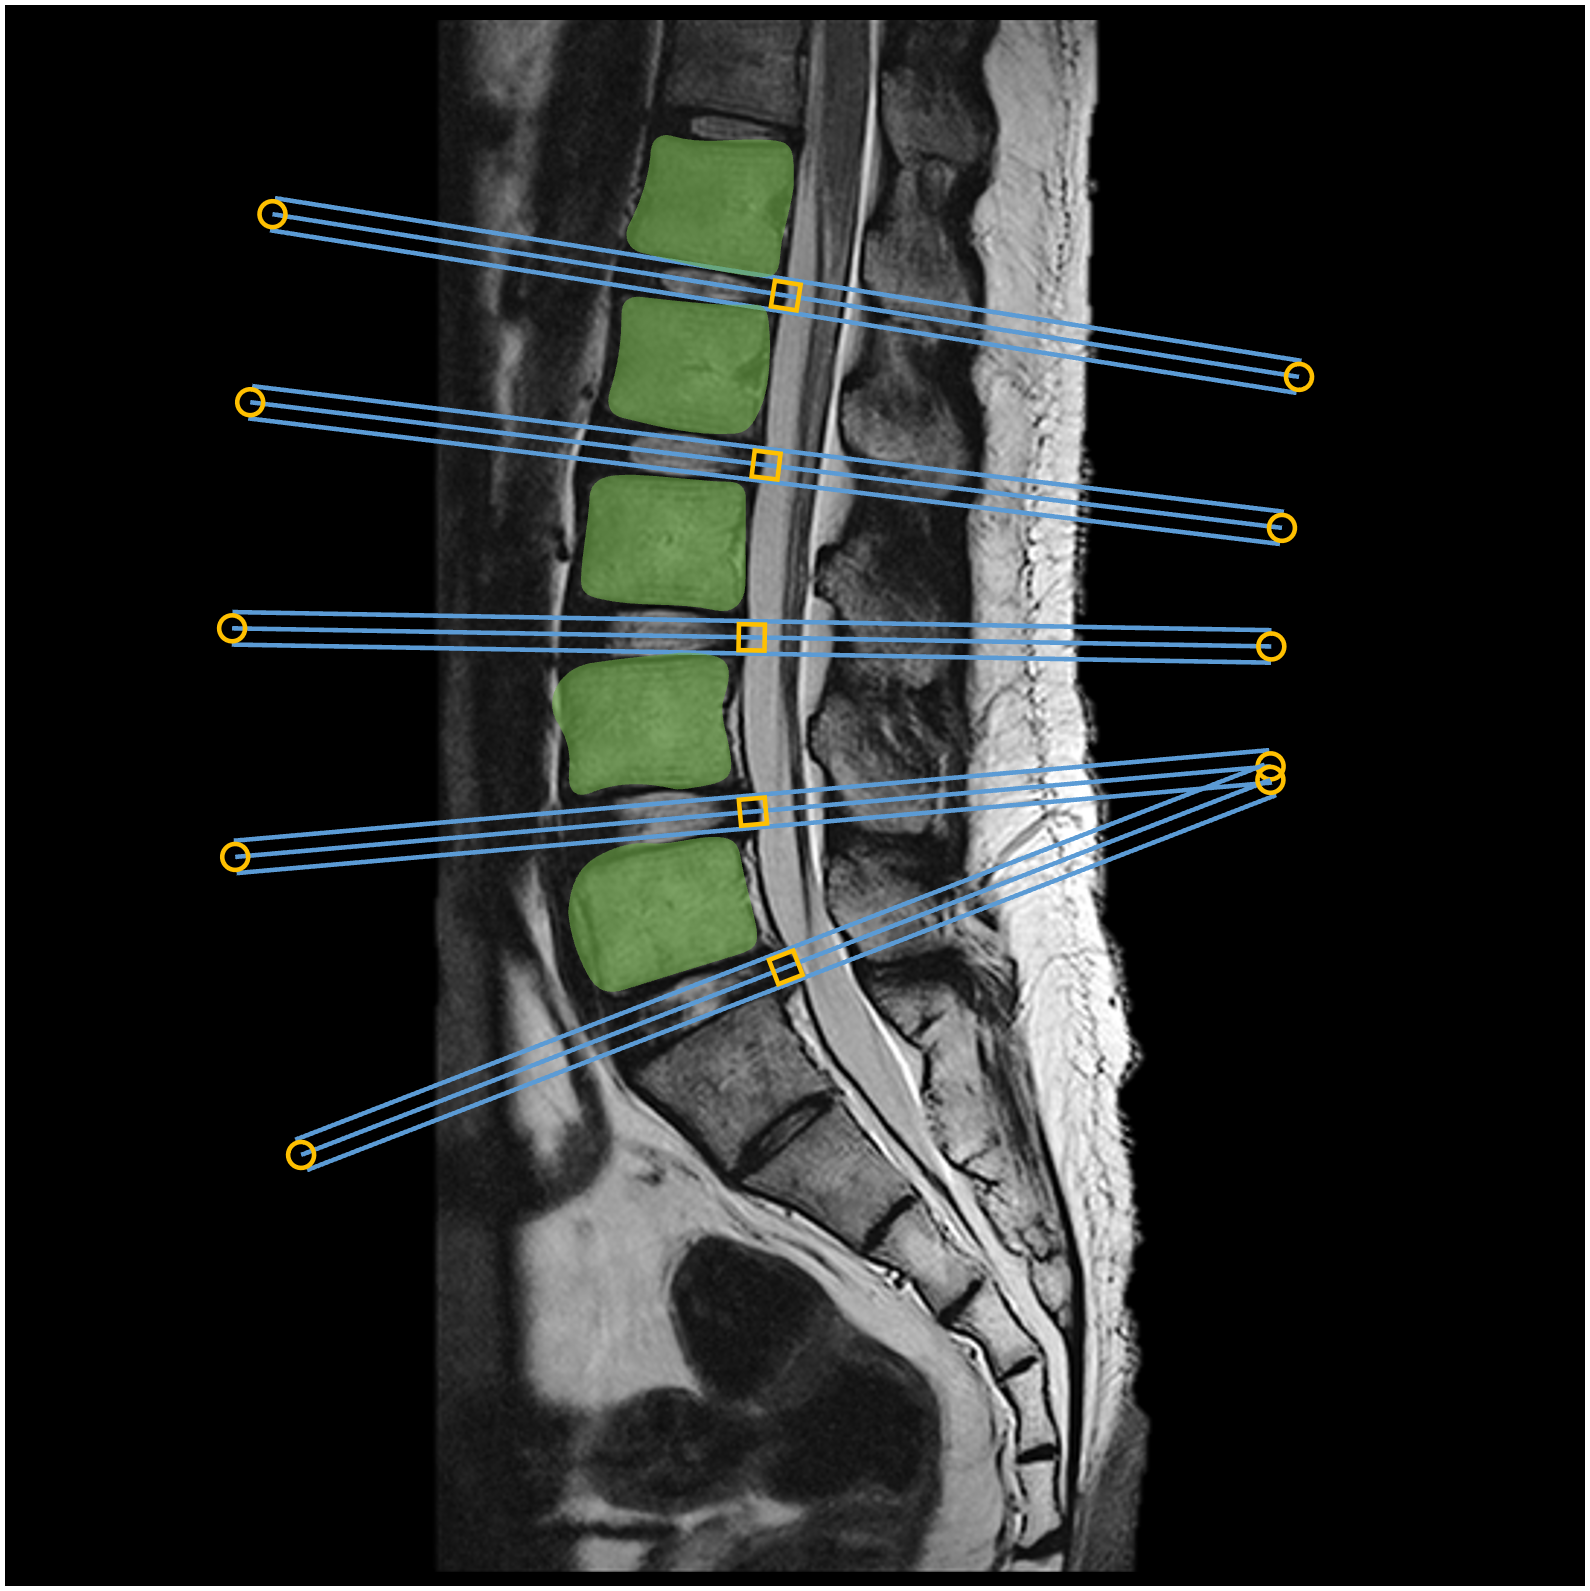

Nền tảng ART

Quy trình làm việc được tối ưu hóa với định vị một lần duy nhất

Động cơ AiTO

Tự động hoàn toàn, hỗ trợ định vị đa hướng

iNavigator

Tối ưu hóa thông số thông minh, đơn giản hóa quá trình hiệu chỉnh